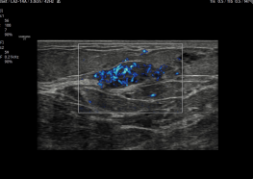

MV-Flow™ y LumiFlow™

Estas tecnologías permiten la visualización de flujo microvascular en 3D y flujos sanguíneos lentos, esenciales para estudios fetales y ginecológicos. MV-Flow™ muestra la intensidad del flujo microvascular en color, mientras que LumiFlow™ ofrece una representación tridimensional del flujo sanguíneo, ayudando a comprender la anatomía vascular de manera intuitiva.

MV-Flow™ y S-Flow™ con LumiFlow™